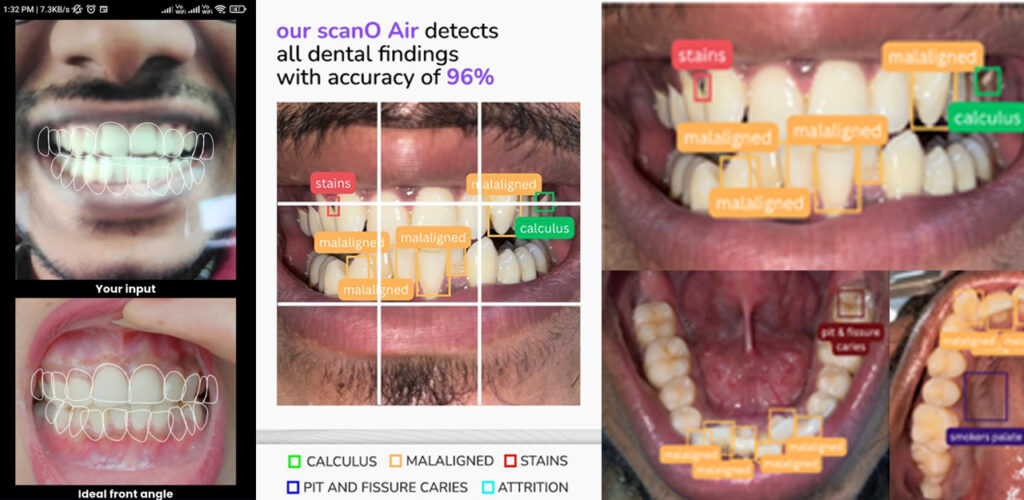

This machine provides rapid diagnostic reports, helping us determine the correct treatment and ensuring patients receive the best care possible.